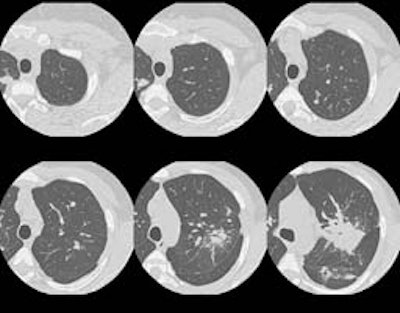

A CT scan of the chest was performed and selected HRCT images were also

obtained: